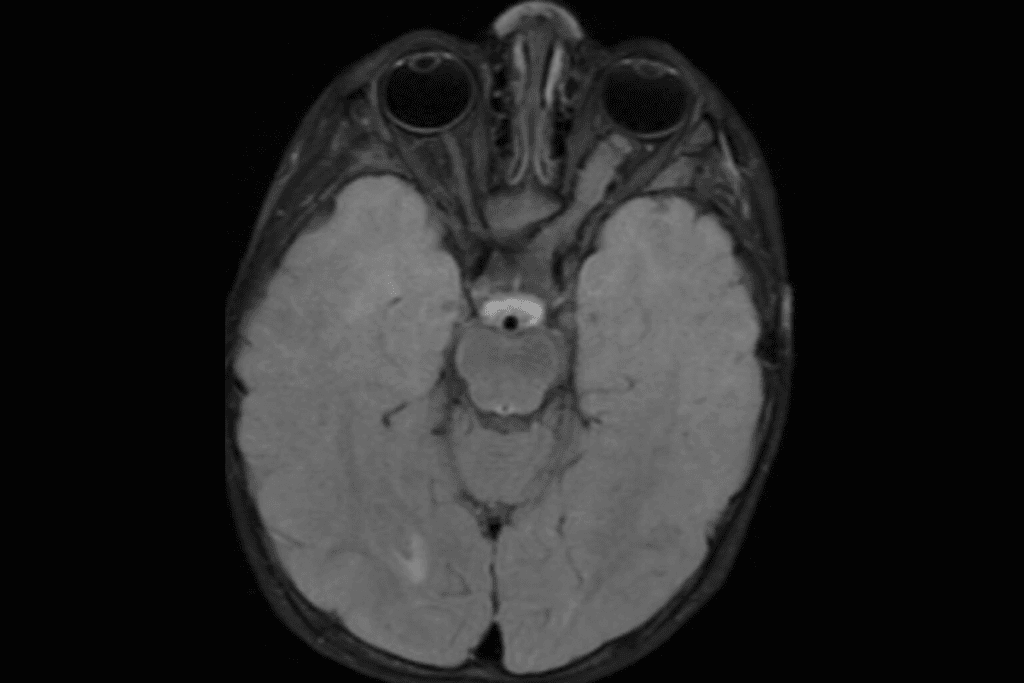

Brain and Central Nervous System Tumors

Brain and CNS tumors are the second most common in kids. They can happen in different parts of the brain and spinal cord. Medulloblastoma and gliomas are common types. Genetic conditions like neurofibromatosis can increase the risk.

“The development of brain tumors in children is often associated with genetic predisposition and certain environmental exposures.” – Expert in Pediatric Oncology

Medical tests are essential for diagnosing childhood tumors. MRI and CT scans show where and how big the tumor is. They also check if it has spread.